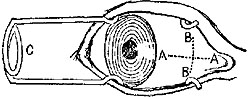

4. As the artery should never be raised from its bed, it is generally advisable to pass the needle only so far as just to permit the eye to be seen past the vessel. The ligature should then be seized by a pair of forceps and gently pulled through, the needle being cautiously withdrawn. When catgut is used, it is better to pass the unarmed needle till the eye is visible, then thread and withdraw it, thus pulling the catgut through.{2}

5. As a rule, the needle should be passed from the side of the vessel at which the chief dangers exist. This will generally be in the side at which the vein is.